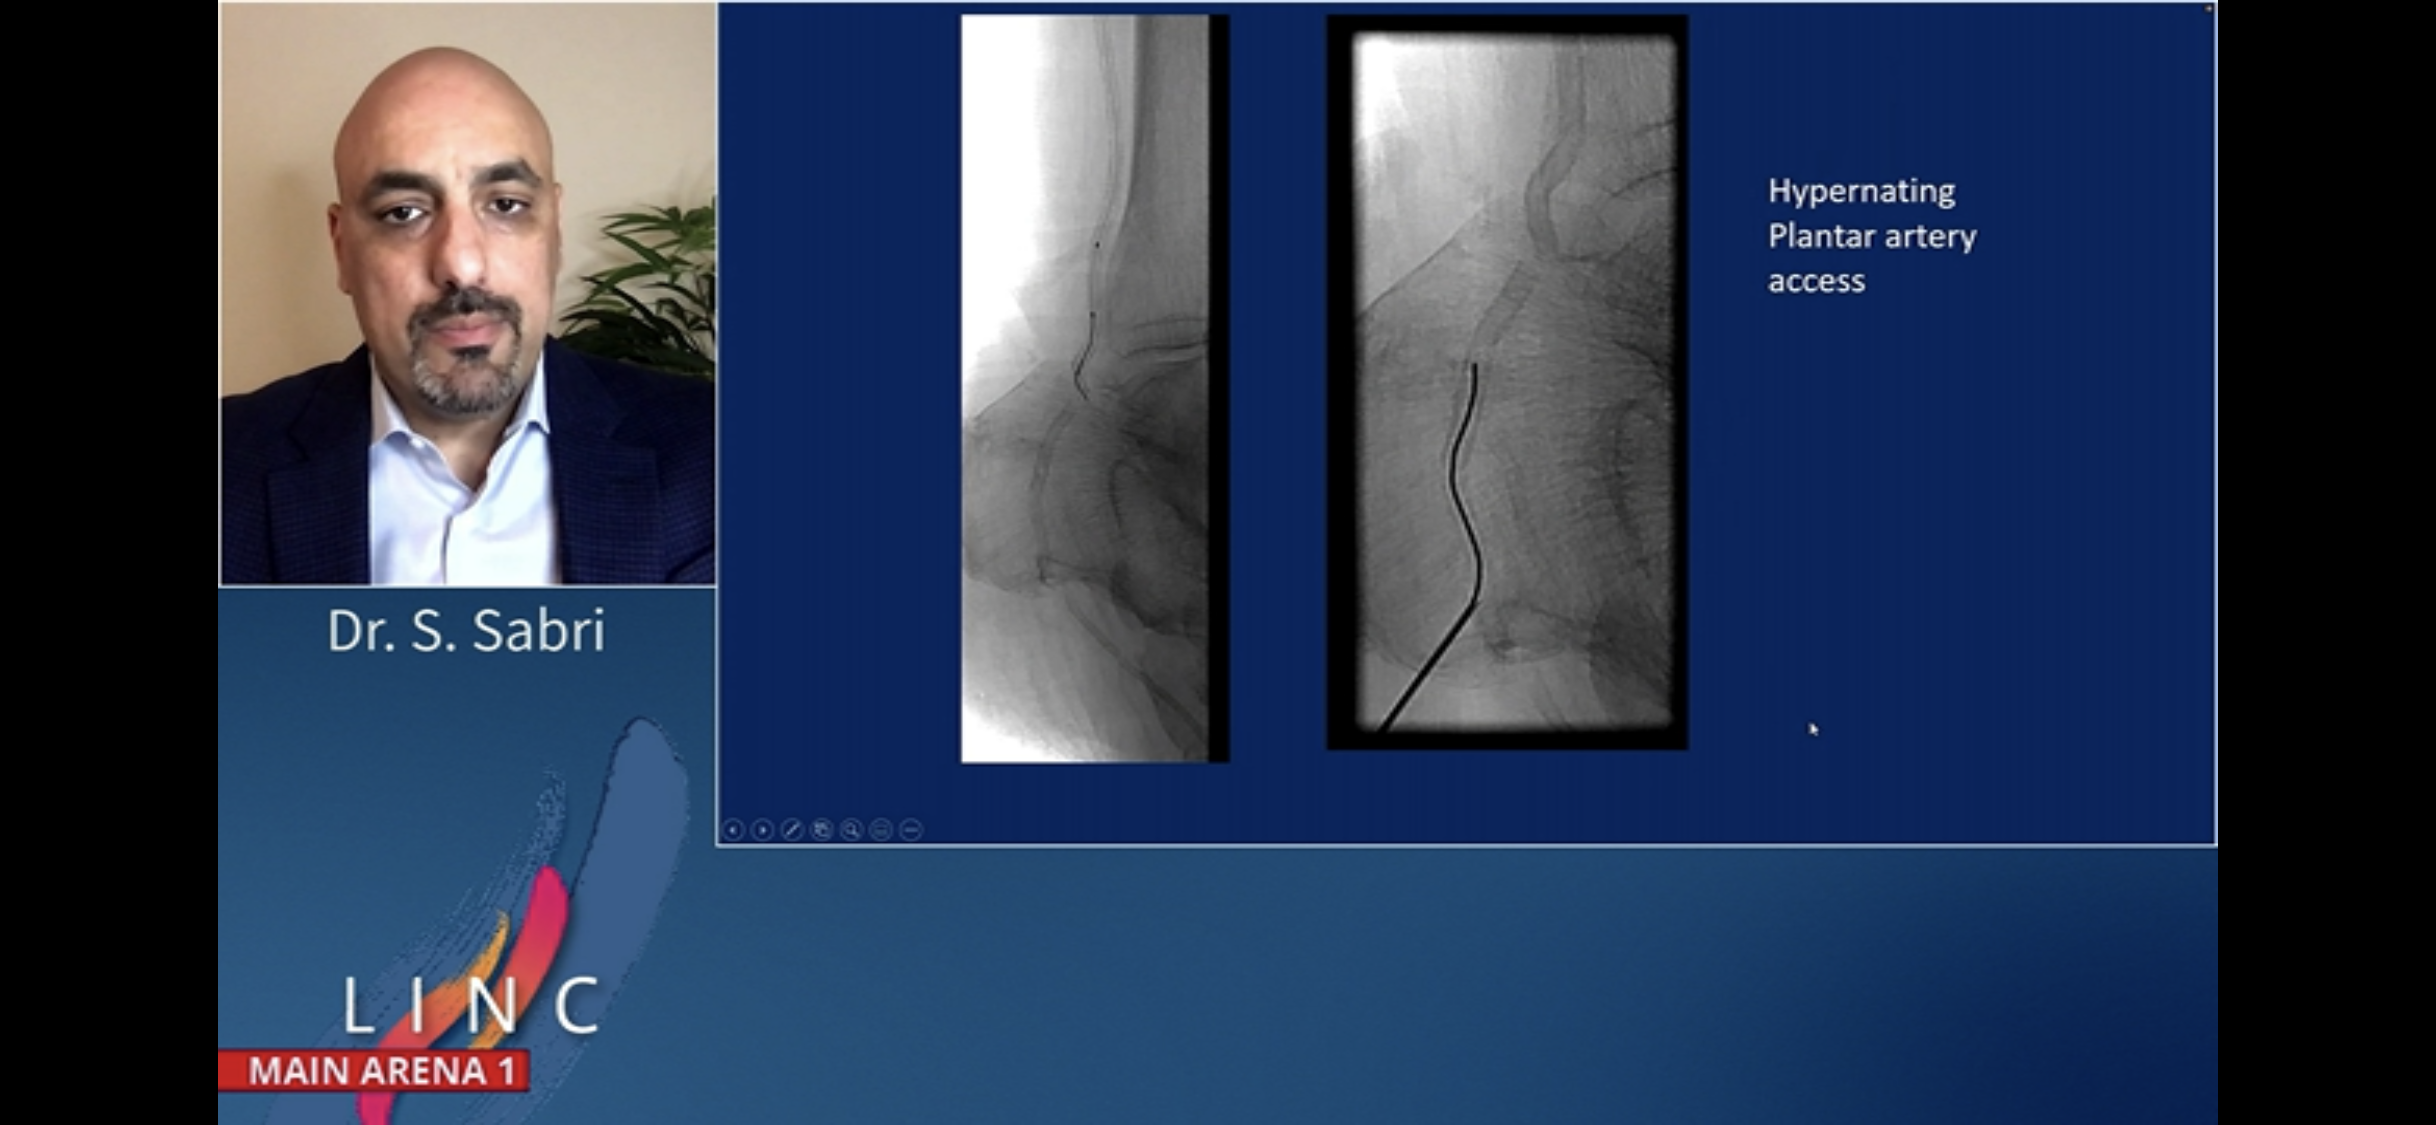

BTK alternative access. Saher Sabri. MA1